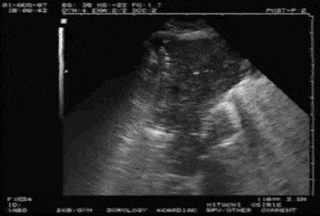

肺点是诊断气胸的金标准。CT图像箭头所指就是胸膜被分离之处(图10)。为什么会出现肺点?在超声图像中,我们可以看到,在分离点的下侧,也就是患者背侧,两个胸膜挨在一起,随着呼吸运动,胸膜有相对滑动,但在分离点以上,超声可以看到壁层胸膜,看不到脏层胸膜,因为它被气体挡住了,超声无法穿透气体,所以我们看到的是没有胸膜滑动的A线,这就是经典的肺点表现。

图片

图10  胸膜分离